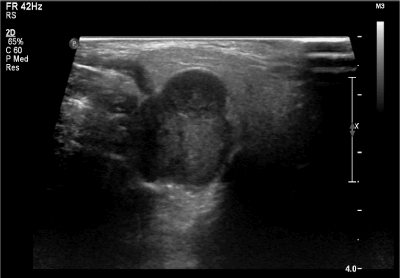

A 31-year-old female of Chinese descent was referred for evaluation of a right neck mass. This mass had been observed by her family doctor for several years and noted to be small and stable in size. However, during the third trimester of her first pregnancy, rapid growth and onset of neuropathic pain along the post-auricular skin in the greater auricular nerve distribution was noted. She had no history of head and neck radiation treatment or a personal or family history of salivary neoplasms. A firm and non-mobile mass was observed to be firmly planted between the mastoid tip and angle of the mandible. At the time of initial assessment, she was noted to have intact facial nerve function and no overlying skin changes. The remainder of her examination was unremarkable. A bedside ultrasonography examination was performed with a 12 MHz linear array probe that demonstrated a lobulated hypoechoic lesion between the mastoid tip and angle of mandible measuring 2.0 X 2.0 X 2.7 cm (Figure 1). Ultrasound-guided fine needle aspirate biopsy demonstrated cytology consistent with adenoid cystic carcinoma.

Figure 1. Ultrasound (12 MHz linear array probe) of right parotid mass demonstrating lobulated hypoechoic lesion between the mastoid tip and angle of mandible measuring 2.0 X 2.0 X 2.7 cm (volume, 5.82 cm3)